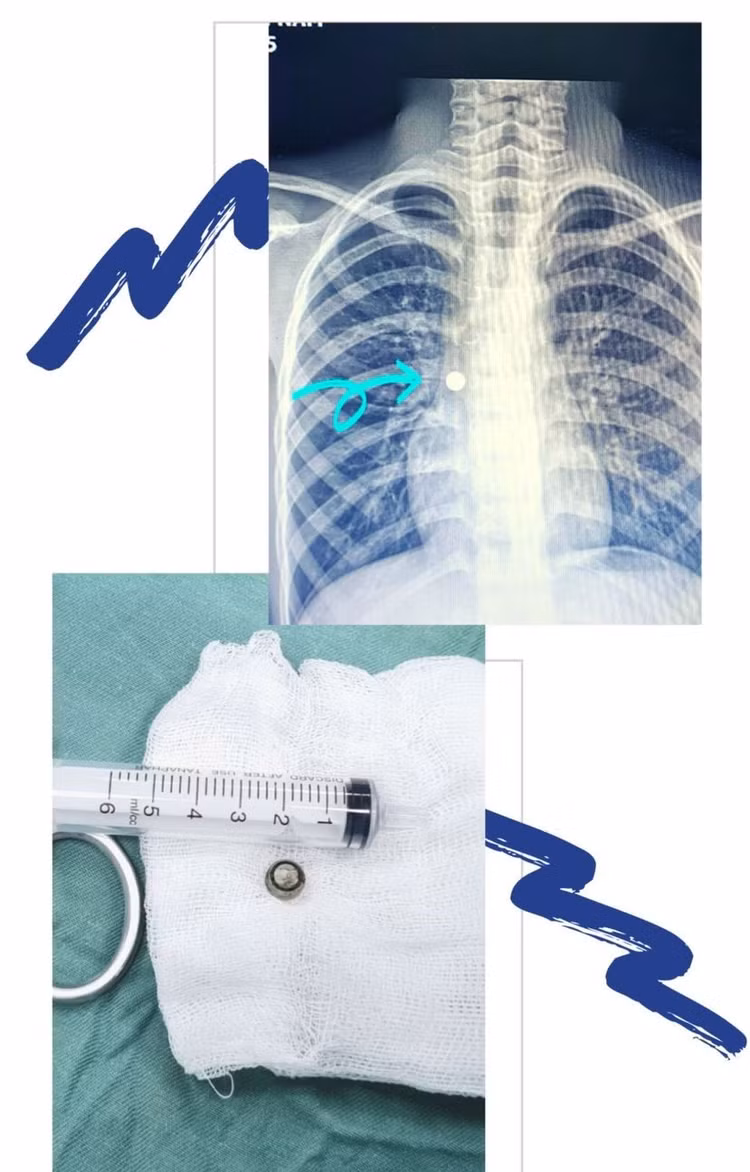

Bệnh nhi được các bác sĩ thăm khám và chỉ định chụp X-quang cấp cứu. Kết quả có hình ảnh dị vật nằm sâu ở phế quản tương ứng phân thuỳ giữa phổi phải. Dị vật này bít tắc gần kín đường thở của trẻ, nếu không được xử trí sớm sẽ gây nguy hiểm đến tính mạng.

![]() |

| Viên pin trong phế quản của trẻ |